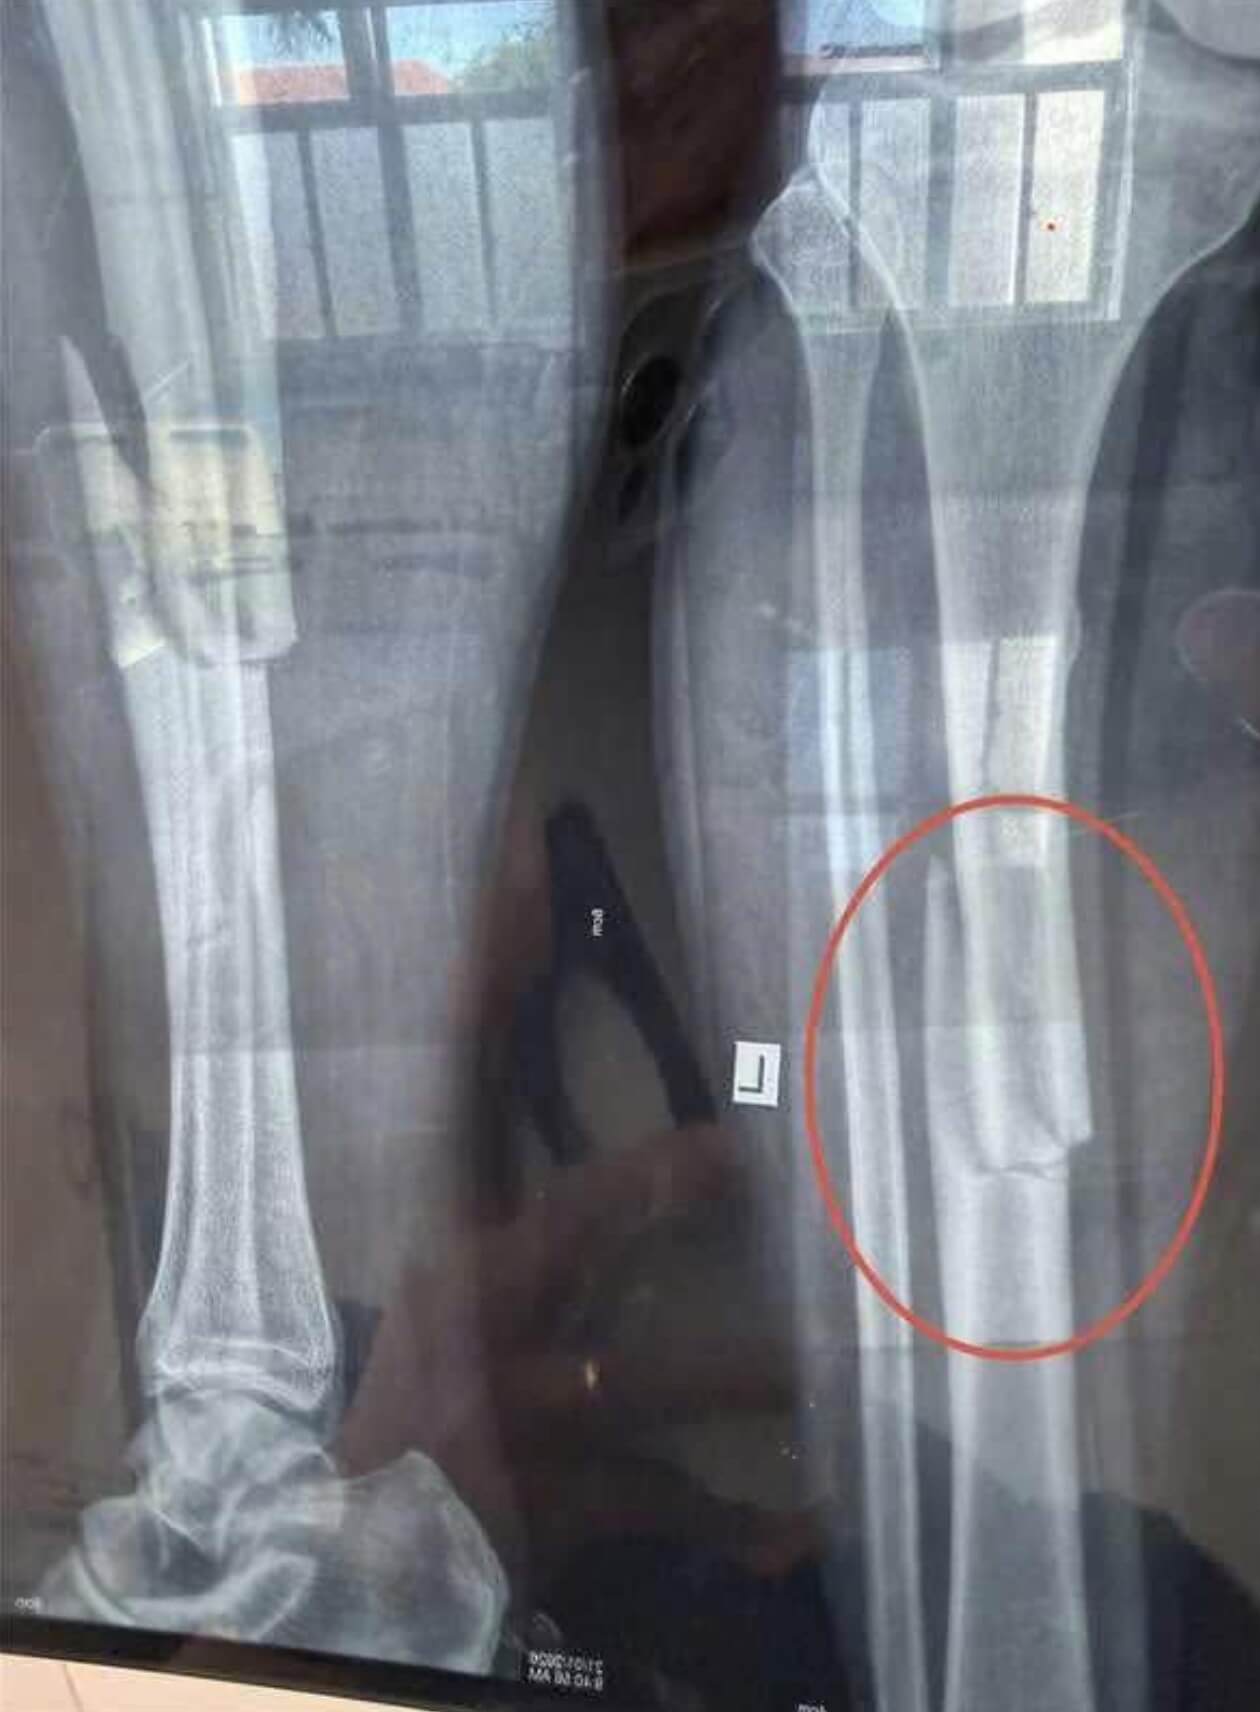

😨😨Tây Ninh-1 vụ tai nạn lao động nghiêm trọng mới đây vừa xảy ra ở 1 nhà máy sản xuất nằm trong KCN Phước Đông khiến 1 nam công nhân trong quá trình làm việc đã bất cẩn bị máy ép cuốn gãy 2 chân,hiện nạn nhân đã được cấp cứu và qua cơn nguy kịch